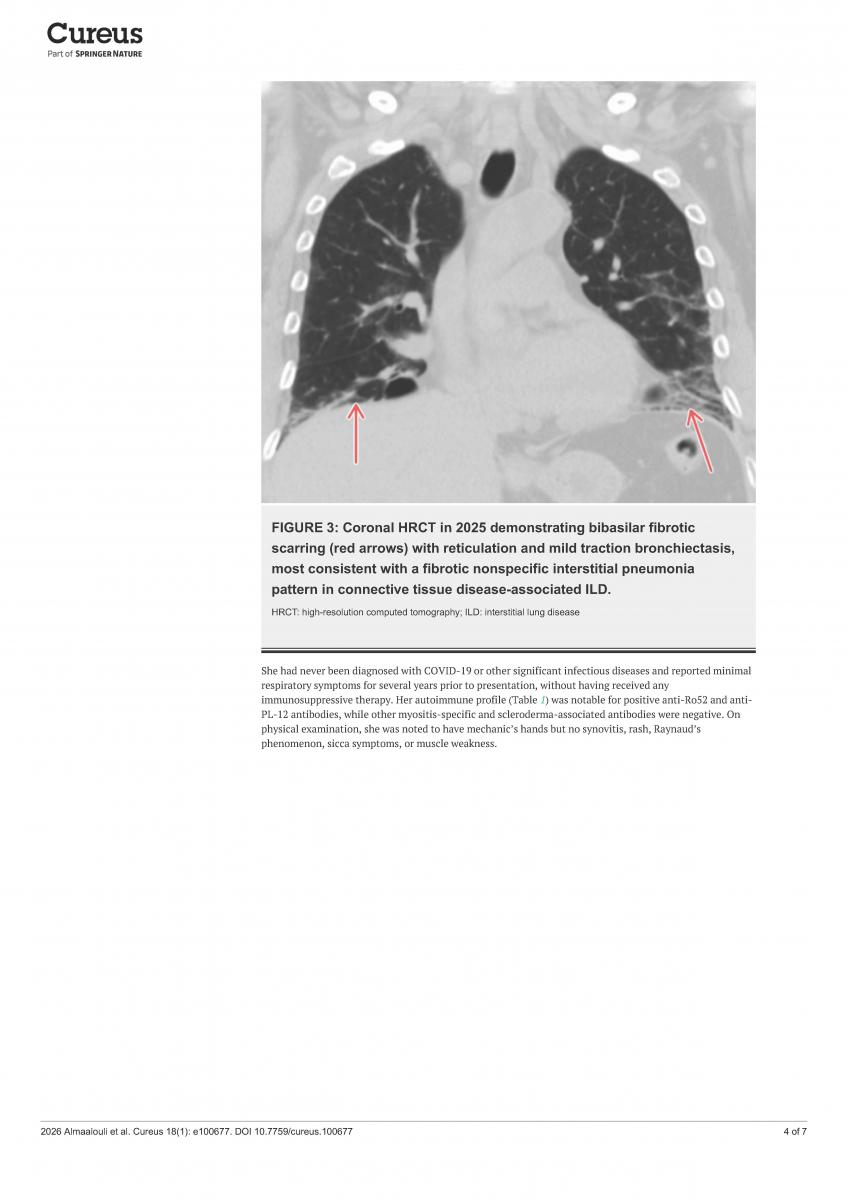

Antisynthetase syndrome (ASS) is a rare autoimmune inflammatory disease. Signs and symptoms include interstitial lung disease, myositis, Raynaud’s phenomenon, joint pain, "mechanic’s hands," and fever. Due to breathing difficulties, the disease is often misdiagnosed as idiopathic pulmonary fibrosis, and delays patients from receiving timely immunosuppressive treatment.